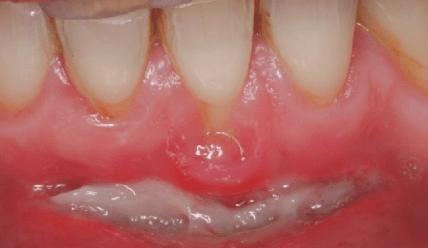

Deckung einer singulären Rezession nach Vorbehandlung mittels Diodenlaser

Diese Fallpräsentation zeigt die vollständige Deckung einer singulären Rezession mittels koronalem Verschiebelappen (KVL) kombiniert mit Einlagerung eines Bindegewebetransplantates (BGT) unter Verwendung eines Diodenlasers (810nm) in der Vorbehandlung. Die Fallpräsentation ist gegliedert in: Patientenstammdaten, Anamnese, Befunde, Diagnose, Ätiologie, Behandlungsplanung, Behandlungsablauf, Schlussbefund, Epikrise und Prognose; abschließend der Spätbefund nach einem Jahr. weiterlesen